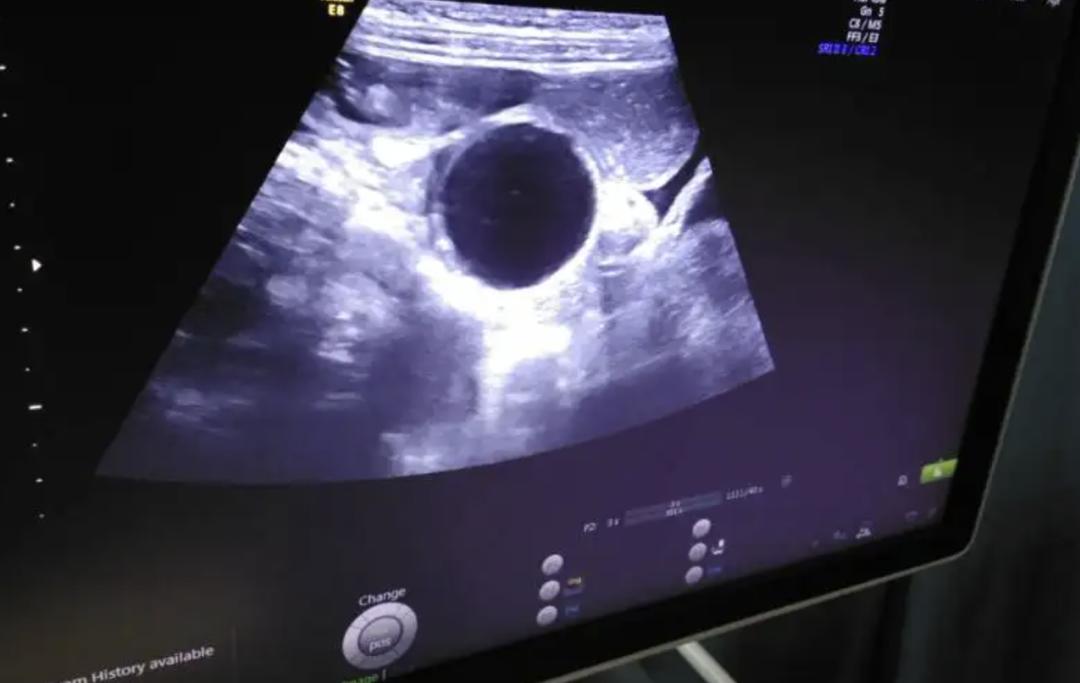

如果怀疑是肠阻塞引起的腹胀,最简单的方法是发作时做腹部X光检查。怀疑是胃或大肠癌性病变患者,可以安排做胃镜或大肠镜检查,特别是年龄超过50岁或有大肠癌家族病史的患者,会建议采取较积极的检查,而不想做侵入性检查的人也可以先初步做粪便潜血检查及抽血检验癌症指数CEA等。而如果怀疑是肝脏、胆囊或腹腔长肿瘤或有腹水等,则可先做腹部超声波检查。如果腹胀的次数很少,或是断断续续好几年,则比较可能是肠胃功能障碍引起的,但如果是最近几周或几个月才有的持续腹胀,加上有大便习惯改变、血便或体重减轻、腹痛、发烧等症状则应尽快就医。